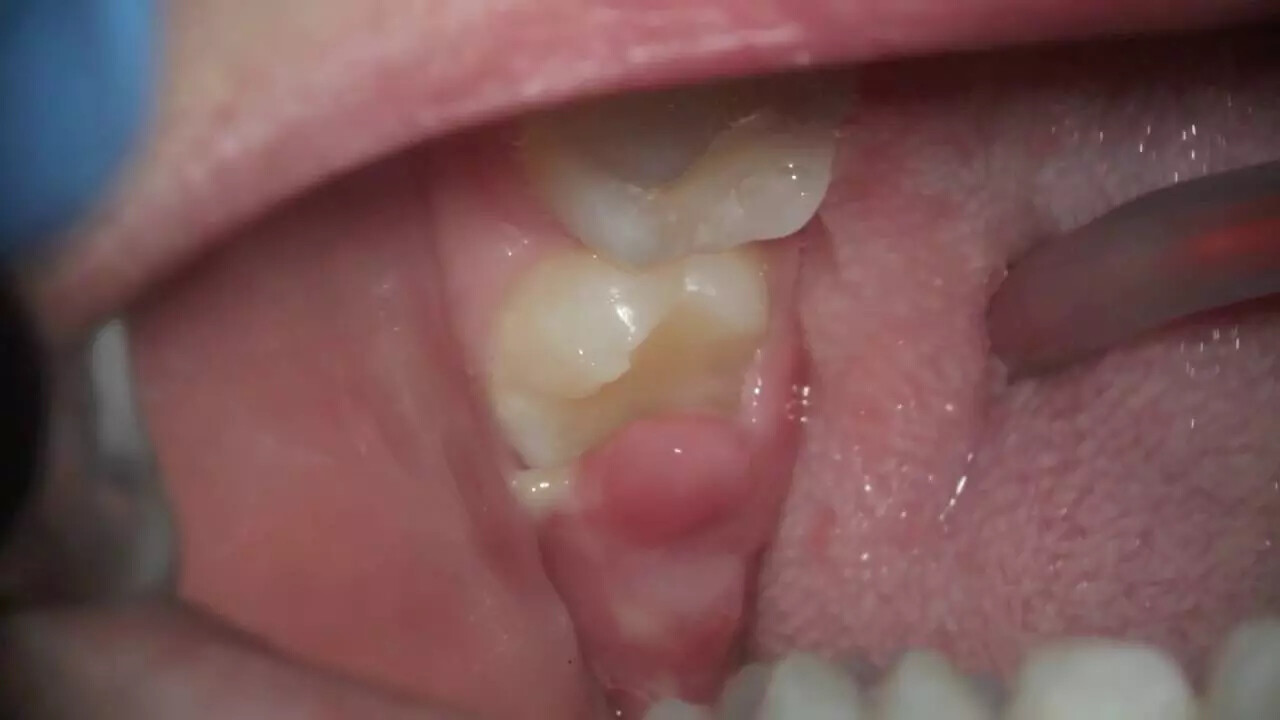

Pericoronitis is the inflammation and infection of tissue surrounding a partially erupted wisdom tooth or teeth, and it’s more common in the lower jaw. Partially impacted molars often have a flap of gum tissue covering the crown of the erupting tooth and this tissue can get food stuck under the gum flap or other debris. This creates a possible breeding ground for bacteria, causing pericoronitis to develop.